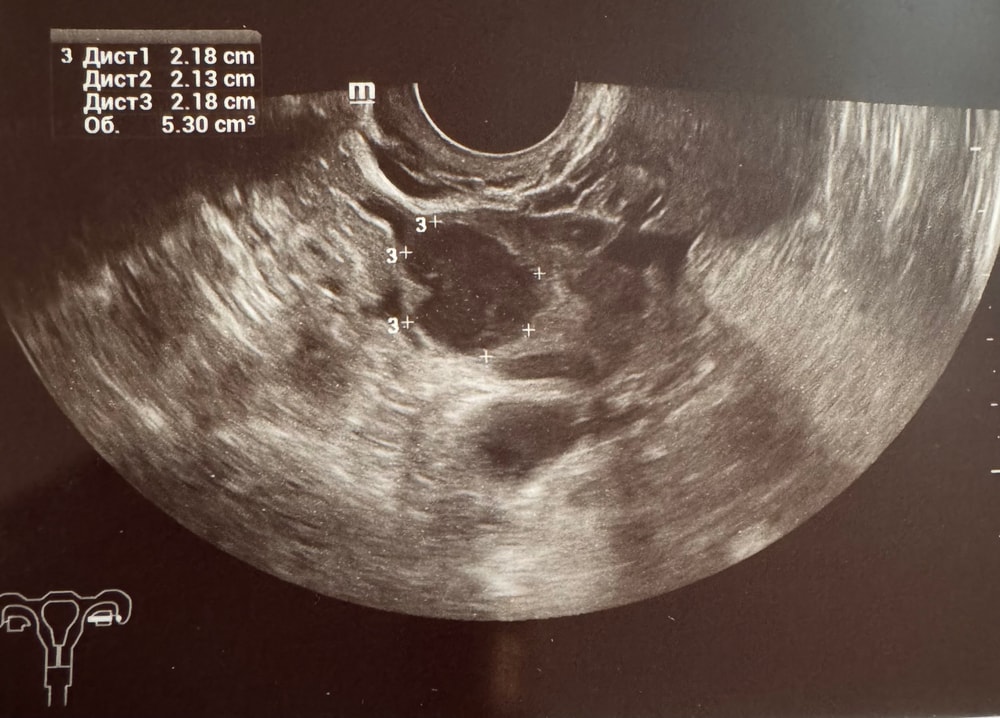

Девочки, помогите разобраться! Была сегодня на УЗИ, врач сказал, что овуляции не было, т.к. эндометрий стал меньше - 8,6 (был в четверг 10,8); жидкости за маткой нет, но при этом написала в заключении: жидкостное образование, ячеистой структуры 22*21*22 мм - киста желтого тела левого яичника. В четверг на УЗИ был ДФ 24*18 мм. Тесты на овуляцию показывали пик ЛГ во вторник. Может ли это быть ЖТ, или это сдувающийся фолликул? И почему эндометрий стал меньше? И врач, и аппарат одни и те же.

Кисты жёлтого тела и жёлтое тело это по сути доказывает что яйце клетка вышла

Кристина, у жт есть кровоток у фоликул нет. Сходите на узи ещё и попросите кровоток посмотреть

Какой-то бред. Конечно была овуляция я считаю. У меня после овуляции эндометрий всегда на 2мм меньше становится так как от прог он уплотняется

Но у вас киста жёлтого тела значит нужно принимать утрожестан. 200-400 в день

Кисты плохо вырабатывает прогестерон по сравнению с обычным желтым телом. И кровоток хуже без подерски никак